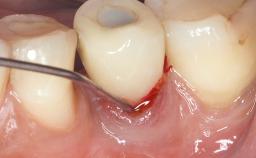

Paolo Casentini and Matteo Chiapasco present a case in which the peri-implant defect was not suitable for a fully regenerative approach. It involves implant removal, use of a CAD/CAM customized titanium mesh in the grafting phase, and placement of new implants. A 62-year-old woman was referred for consultation regarding her implant-supported prosthesis replacing teeth 14 to 16. The patient’s main concern was pain and recurrent swelling in the right posterior maxilla. The patient also reported difficulty and discomfort when brushing the area. The patient reported she had been treated in another country, where she had received three implants in combination with sinus-floor augmentation for the replacement of the posterior maxillary teeth three years earlier. The patient indicated “endodontic complications” to be the reason for the extraction of the teeth.